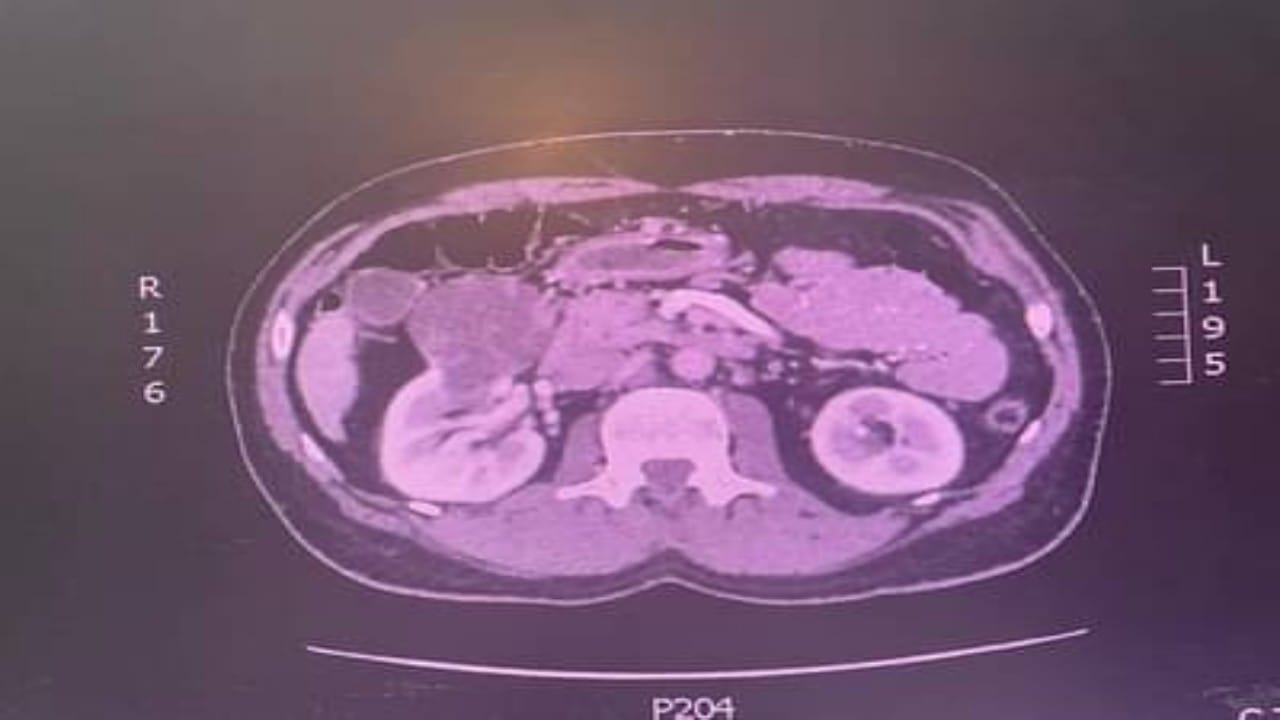

استئصال ورم كلوي لمريض خمسيني في الطائف

“سعود الطبية” توضح أسباب استسقاء الكلية وأعراضها